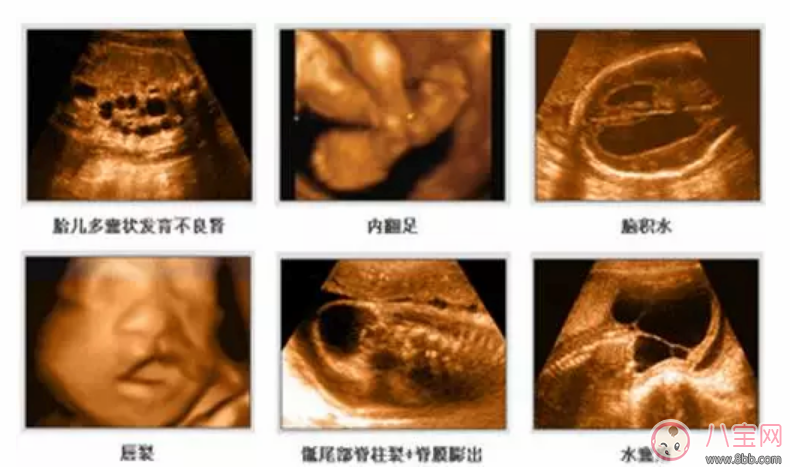

2、四維彩超能多方位,多角度地診斷胎兒各器官的發育情況,可以精確篩查先天性畸形,例如骨骼發育異常、唇裂等癥狀,有利于胎兒早期診斷治療。

3、四維彩超能對胎兒的體表進行檢查,能夠準確、清晰檢測出胎兒發育是否異常,及早檢查胎兒的大腦、脊柱、骨骼、面部是否有發育不良的情況,以便盡早的進行治療。